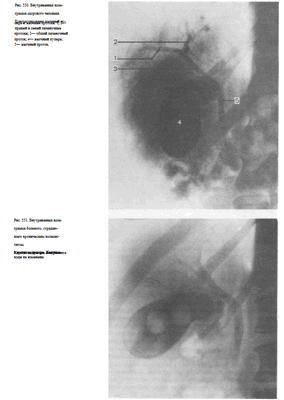

При выделительной холецистохолангиографии на снимках отчетливо видны печеночные протоки, общий желчный проток, пузырный проток, а также желчный пузырь (рис. 550). Интенсивность выделения препарата печенью характеризует и ее выделительную функцию.

Выделительная холеграфия дает возможность выявить холестериновые камни как желчного пузыря, так и расположенных в желчных протоках, а также исследовать желчные пути после холецистэктомии (рис. 551).

Не удаляя иглы с помощью переносного или палатного аппарата производят рентгеновский снимок (кассету подкладывают под больного заранее) и подвергают его срочной фотообработке. Перед рентгенографией хирургические инструменты стремятся расположить вне проекции желчных путей (рис. 552).